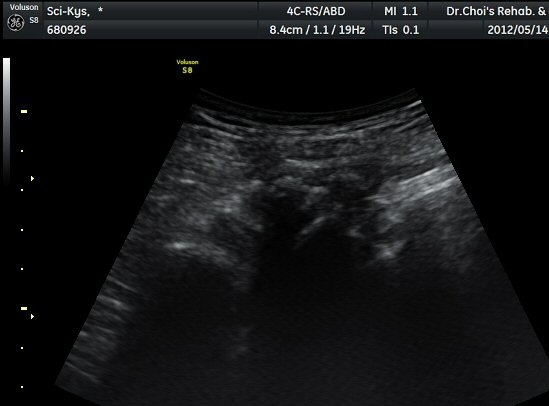

ŽÃËÀÚ¸¦ ¾à°£ ±ÙÀ§ºÎ·Î À̵¿ÇÏ´Ï °æ°è°¡ ºÒºÐ¸íÇÑ »À°¡ Á°ñ½Å°æ ¿ÜÃø¿¡¼­ µ¹ÃâÇϸ鼭

Á°ñ½Å°æÀ» ³»ÃøÀ¸·Î ½ÉÇÏ°Ô ÀüÀ§½ÃŲ´Ù(±×¸² 4, 5).